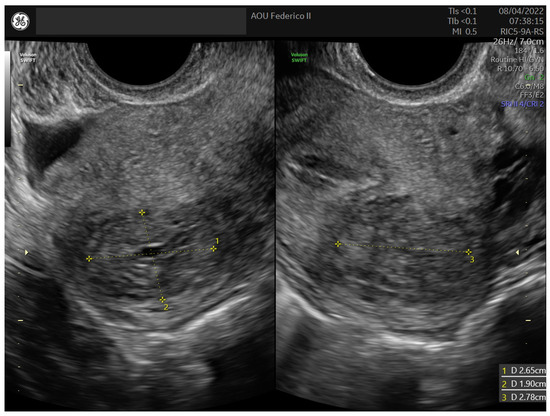

2.2. Case 2